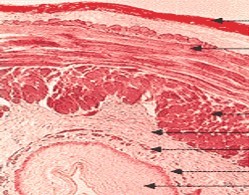

Name these layers

Serosa

Longitudinal muscle

Circular muscle

Submucosae

Muscularis mucosae

Lamina propia

Epithelium